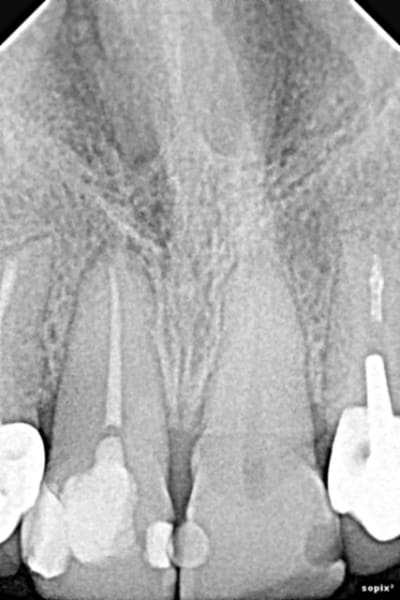

Patiente 58 ans. En bonne santé (physique et financière). Son souhait : quelque chose qui dure et sur lequel elle ne reviendra pas...

Moi j'aime pas l'apex de la 12... Préviens là quand même que ça peut ne pas durer si longtemps que ça pour cette dent. (idem 22)

Là est tout le problème... quel est l'avenir de ces dents antérieures ??

Est-ce que ça vaut le coup de les garder ? est-ce qu'on a 90% de chance que dans 5 ans la moitié soient à extraire...

3 sans hésiter (je ne vois pas grand chose sur la pano, trop petite sur mon écran)

Au scanner, il est complètement obstrué certainement à cause du bout de pâte ou autre que l'on peut apercevoir sur la pano.

La question à 15k€, pourquoi elle a perdu ses dents? Ça commence un peu en bas aussi non, la paro sur molaires ?

Certaines des dents antérieures me paraissent courtes (la 22 en particulier): serait-il possible de les mesurer avec le logiciel?

Sinon, je ne vois pas pourquoi il ne serait pas possible de les garder avec un traitement canalaire bien réalisé + IC + couronnes solidarisées.